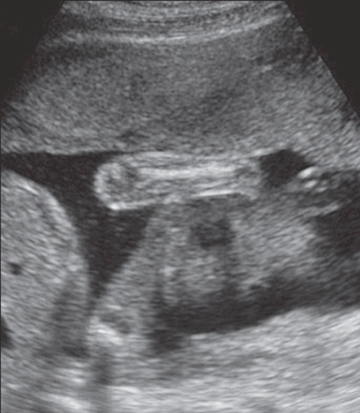

duodenal atresia